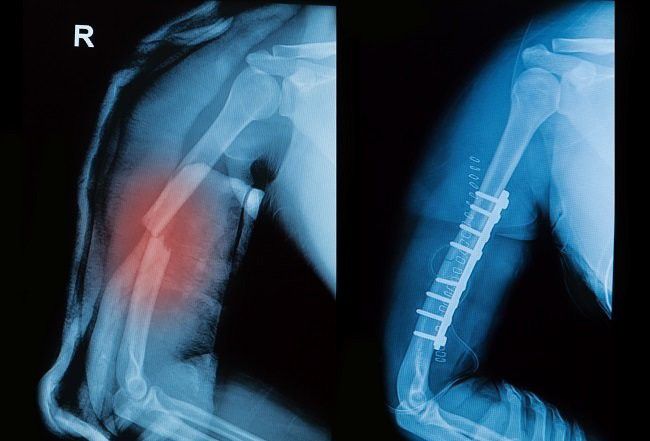

Patah tulang lenngan atas (alodokter.com)